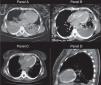

A previously healthy 28-year-old woman was admitted on the intensive care unit with a diagnosis of septic shock. Her blood pressure was 50/40mm Hg and presented signs of systemic hypoperfusion, including obnubilation. A chest computed tomography revealed pneumonia and bilateral pulmonary pleural effusion (Fig. 1: panel A). The patient required hemodynamic and ventilatory support, broad spectrum antibiotics and a bilateral thoracic drainage. The results of pleural fluid analysis were compatible with empyema; in the culture we were able to isolate Klebsiella pneumoniae. A new TC scan was repeated six days after the admission and found improvement on the pulmonary infiltrate, persistence of the pleural effusion and an unexplained myocardial left ventricular calcification1 (Fig. 1: panel B). She was discharged in a stable condition, with persistent tachycardia and a pleuritic chest pain. 20 days after being discharged, she returned for a routine control, presenting chest pain and tachycardia. The new CT revealed a minimal pleural effusion and radiologic improvement of the pneumonia with an increase in the density and distribution of the calcification in the left ventricle2 (Fig. 1: panels C and D). The pathophysiology of myocardial calcification is not fully explained. Usually, it represents the sequel of a local tissue damage, impaired membrane or cellular necrosis and is not associated with abnormalities in serum calcium levels or calcium metabolism. The most common cause is myocardial infarction, but it has also been reported in the context of trauma, infections, inflammatory or neoplastic processes.3

Panel A. Tomography performed on admission showing bilateral pleural effusion and pulmonary consolidation. Panel B. Similar tomography slice obtained 7 days later, revealing calcified ventricular myocardium. Panels C and D. Extensive calcification throughout the left ventricular myocardium (day 30).